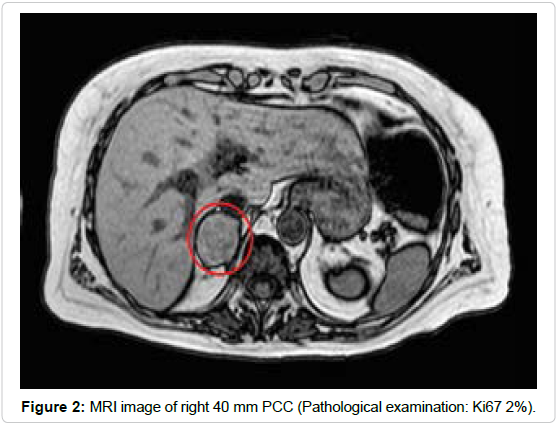

However, despite normalization of coagulation parameters, renal function and LVEF, high levels of direct bilirubin persisted, and patient developed sub-icterus. An abdominal echo scan was then performed, identifying dilated biliary ducts, without hepatic masses or alterations; kidneys were normal, but a right adrenal incidentaloma was discovered. To confirm the diagnosis for biliary tract pathology, an MRI diagnosed the presence of an ampulloma (20 mm) but it also evidenced left (6 mm) and right (40 mm) masses of adrenal glands (Figures 1, 2 and 3). High concentrations of urine and plasma free metanephrines (p-normetanephrines: 1518 and 2480 pmol/L, p-metanephrines: 3313 and 4222 pmol/L, u24h-normetanephrines: 437 and 509 mcg/die, u24h-metanephrines: 1386 and 1830 mcg/die), high Chromogranin A (>1100 ng/mL) and neuron specific enolase (19.6 ng/mL) levels suggested the diagnosis of pheochromocytoma (PCC). The presence of distant metastasis was excluded with brain-neck-thoracic CT scan and with 123I-MIBG and 111In-Pentetreotide Scintigraphies. Both imaging methods showed surprisingly a more intense tracers’ uptake from left PCC without visualizing the ampulloma.

Figure 2. MRI image of right 40 mm PCC (Pathological examination: Ki67 2%).

All tumors were surgically removed without complications. Pathologist confirmed the diagnosis of bilateral PCC (right adrenal gland: PCC of 40 mm, Ki67 2%; left adrenal gland: PCC of 5 mm with vascular invasion, profound nuclear pleomorphism, mitosis 6x 10 HPF, Ki67 9%) and of ampullary neuroendocrine tumor (G2 with muscular invasion – pT2 N0 M0). Results from genetic analysis confirmed the mutation in NF-1 gene. After 3 year of regular follow-up, the patient presents good clinical conditions and has neither biochemical nor radiological evidence of disease recurrence.